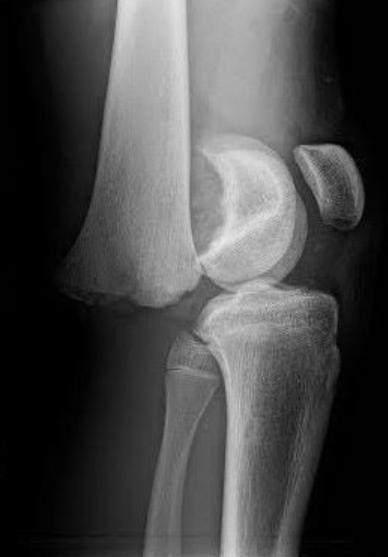

A 21-year-old female presents to the emergency room after falling from dancing on a table and injuring her right ankle. She is in severe pain and unable to bear weight comfortably with swelling and tenderness along the lateral malleolus. X-rays are taken and shown above.